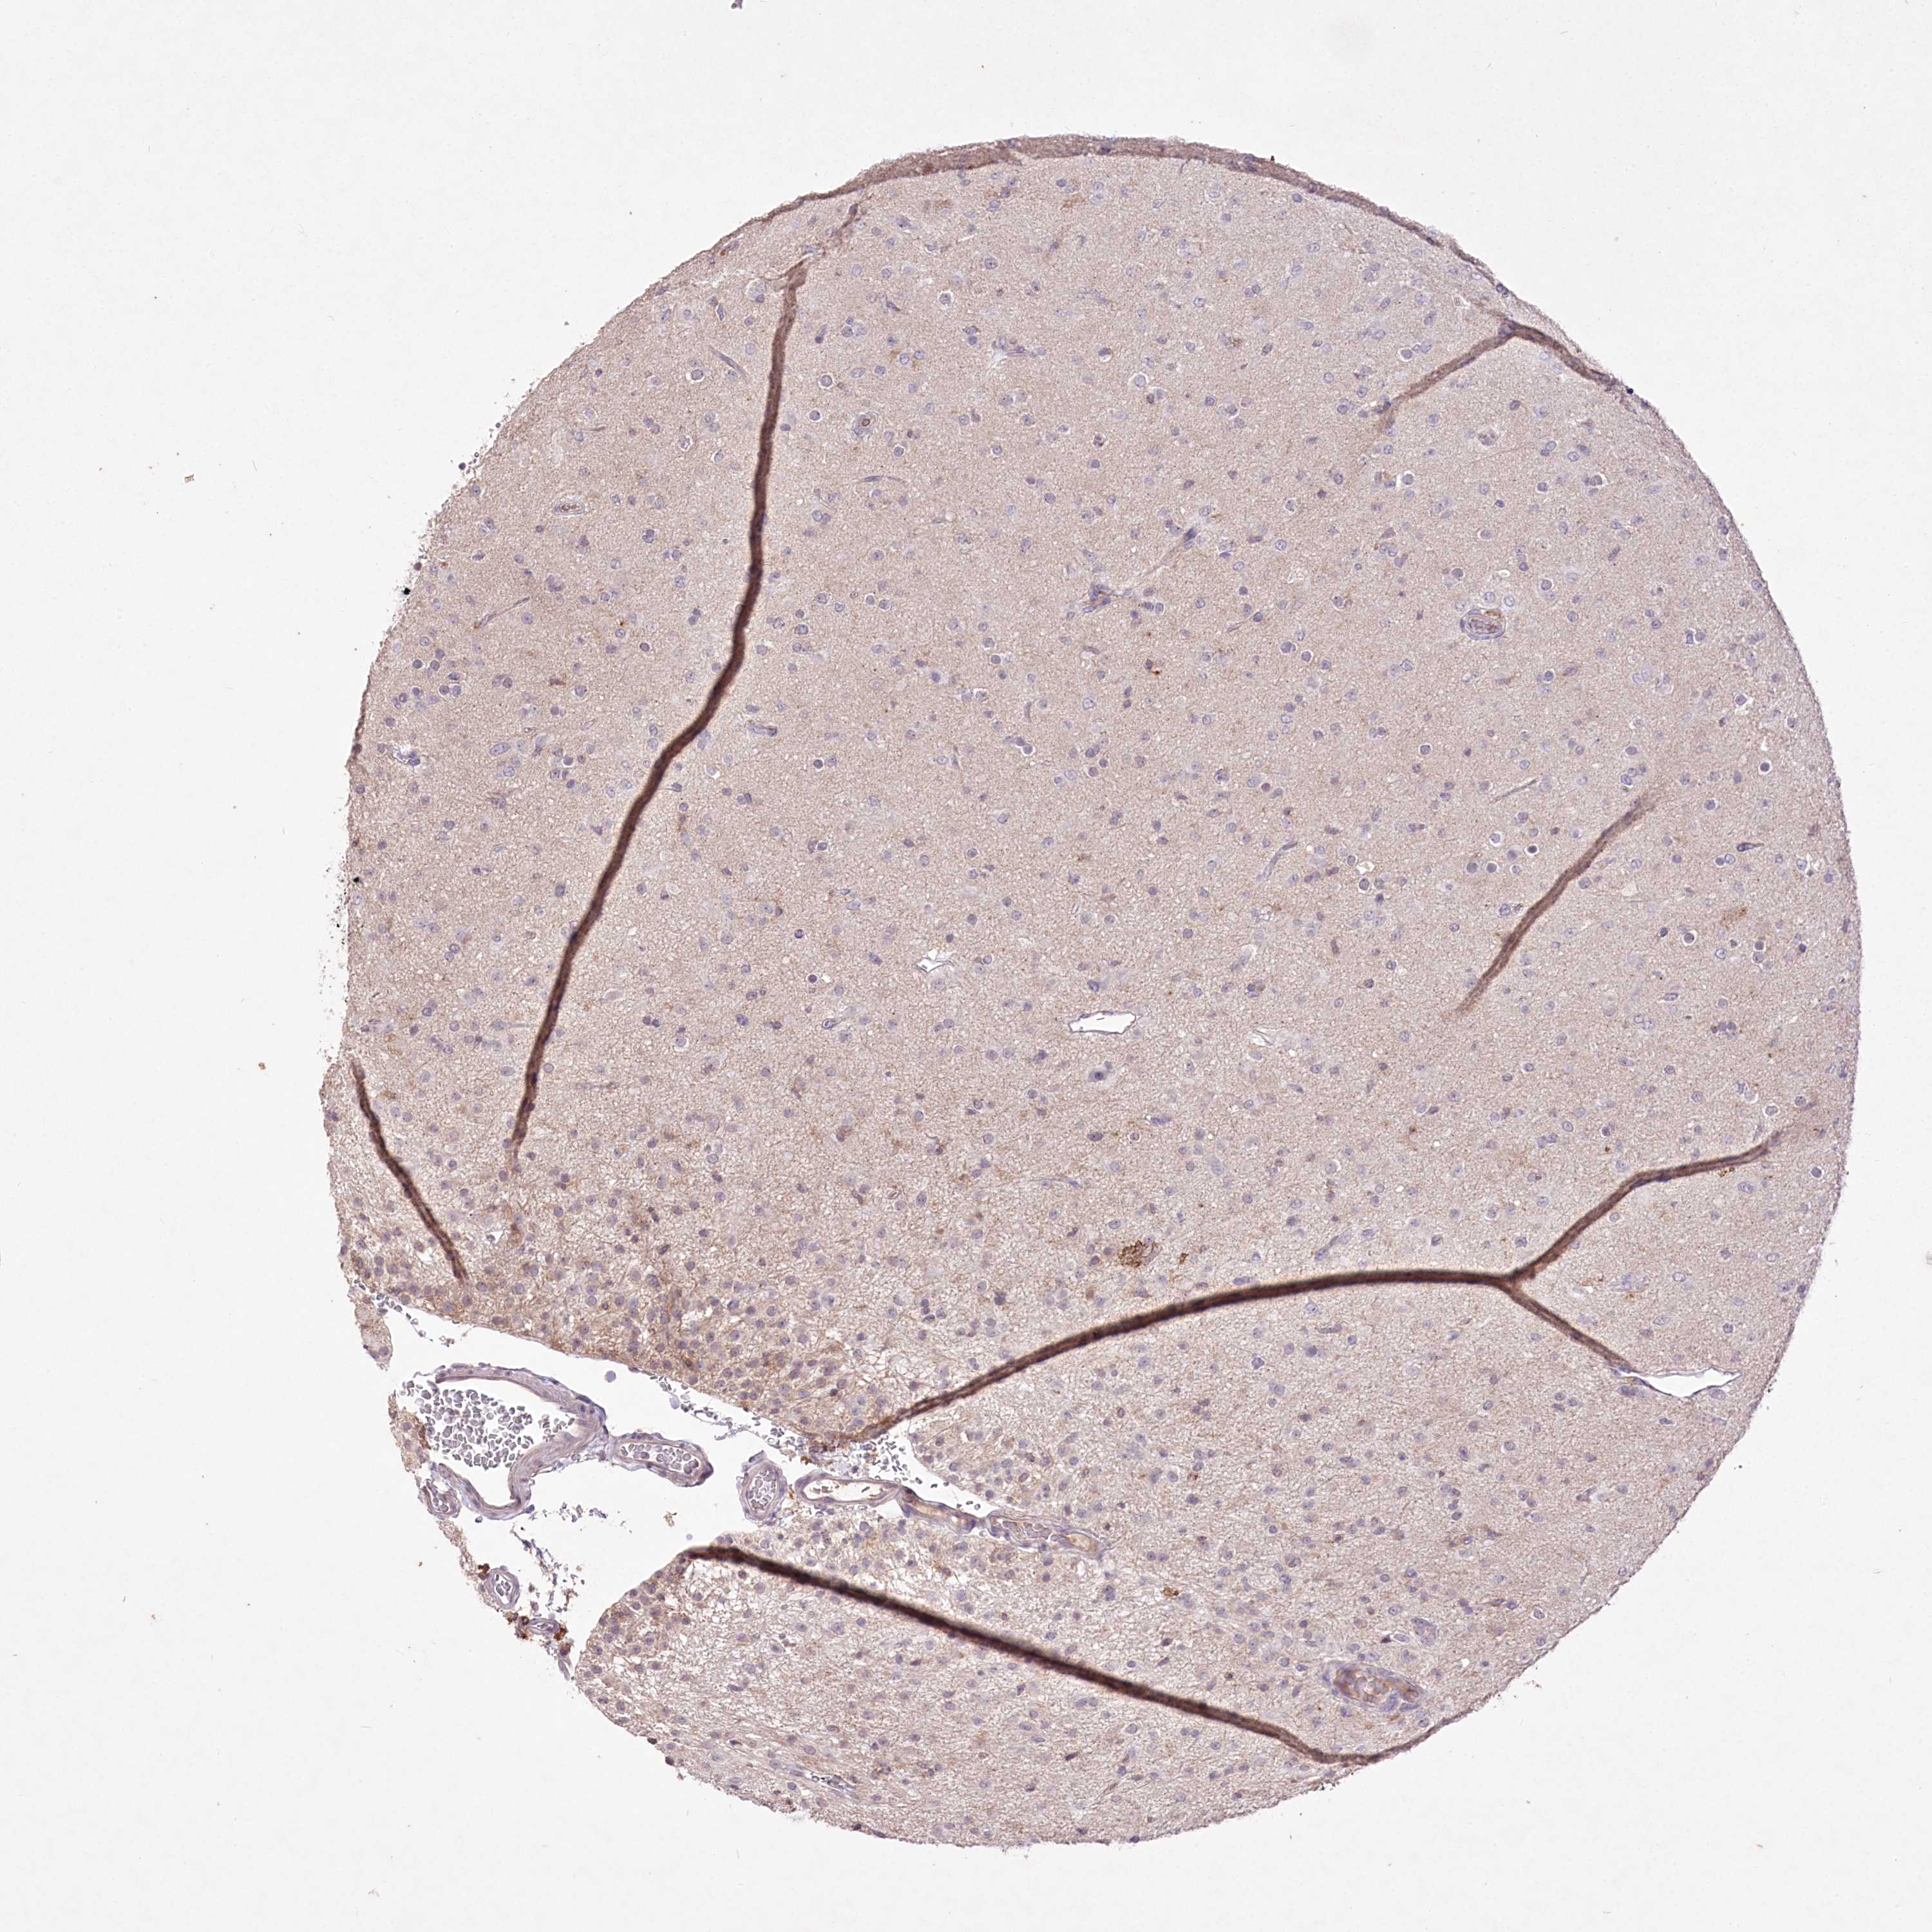

GLIOMA - Protein expressioni

A mouse-over function shows sample information and annotation data. Click on an image to view it in a full screen mode. Samples can be filtered based on level of antibody staining by selecting one or several of the following categories: high, medium, low and not detected. The assay and annotation is described here.

Note that samples used for immunohistochemistry by the Human Protein Atlas do not correspond to samples in the TCGA dataset.

Antibody stainingi

Antibody staining in the annotated cell types in the current human tissue is reported as not detected, low, medium, or high, based on conventional immunohistochemistry profiling in selected tissues. This score is based on the combination of the staining intensity and fraction of stained cells.

Each image is clickable and will lead to virtual microscopy that enables deeper exploration of all samples and also displays staining intensity scores, fraction scores and subcellular localization as well as patient and tissue information for each sample.

Antibody HPA062066

Antibody CAB032904

Staining

High

Medium

Low

Not detected

Intensity

Strong

Moderate

Weak

Negative

Quantity

>75%

75%-25%

<25%

None

Location

Nuclear

Cytoplasmic/membranous

Cytoplasmic/membranous,nuclear

Glioma, malignant, Low grade

Glioma, malignant, High grade

Glioblastoma, NOS